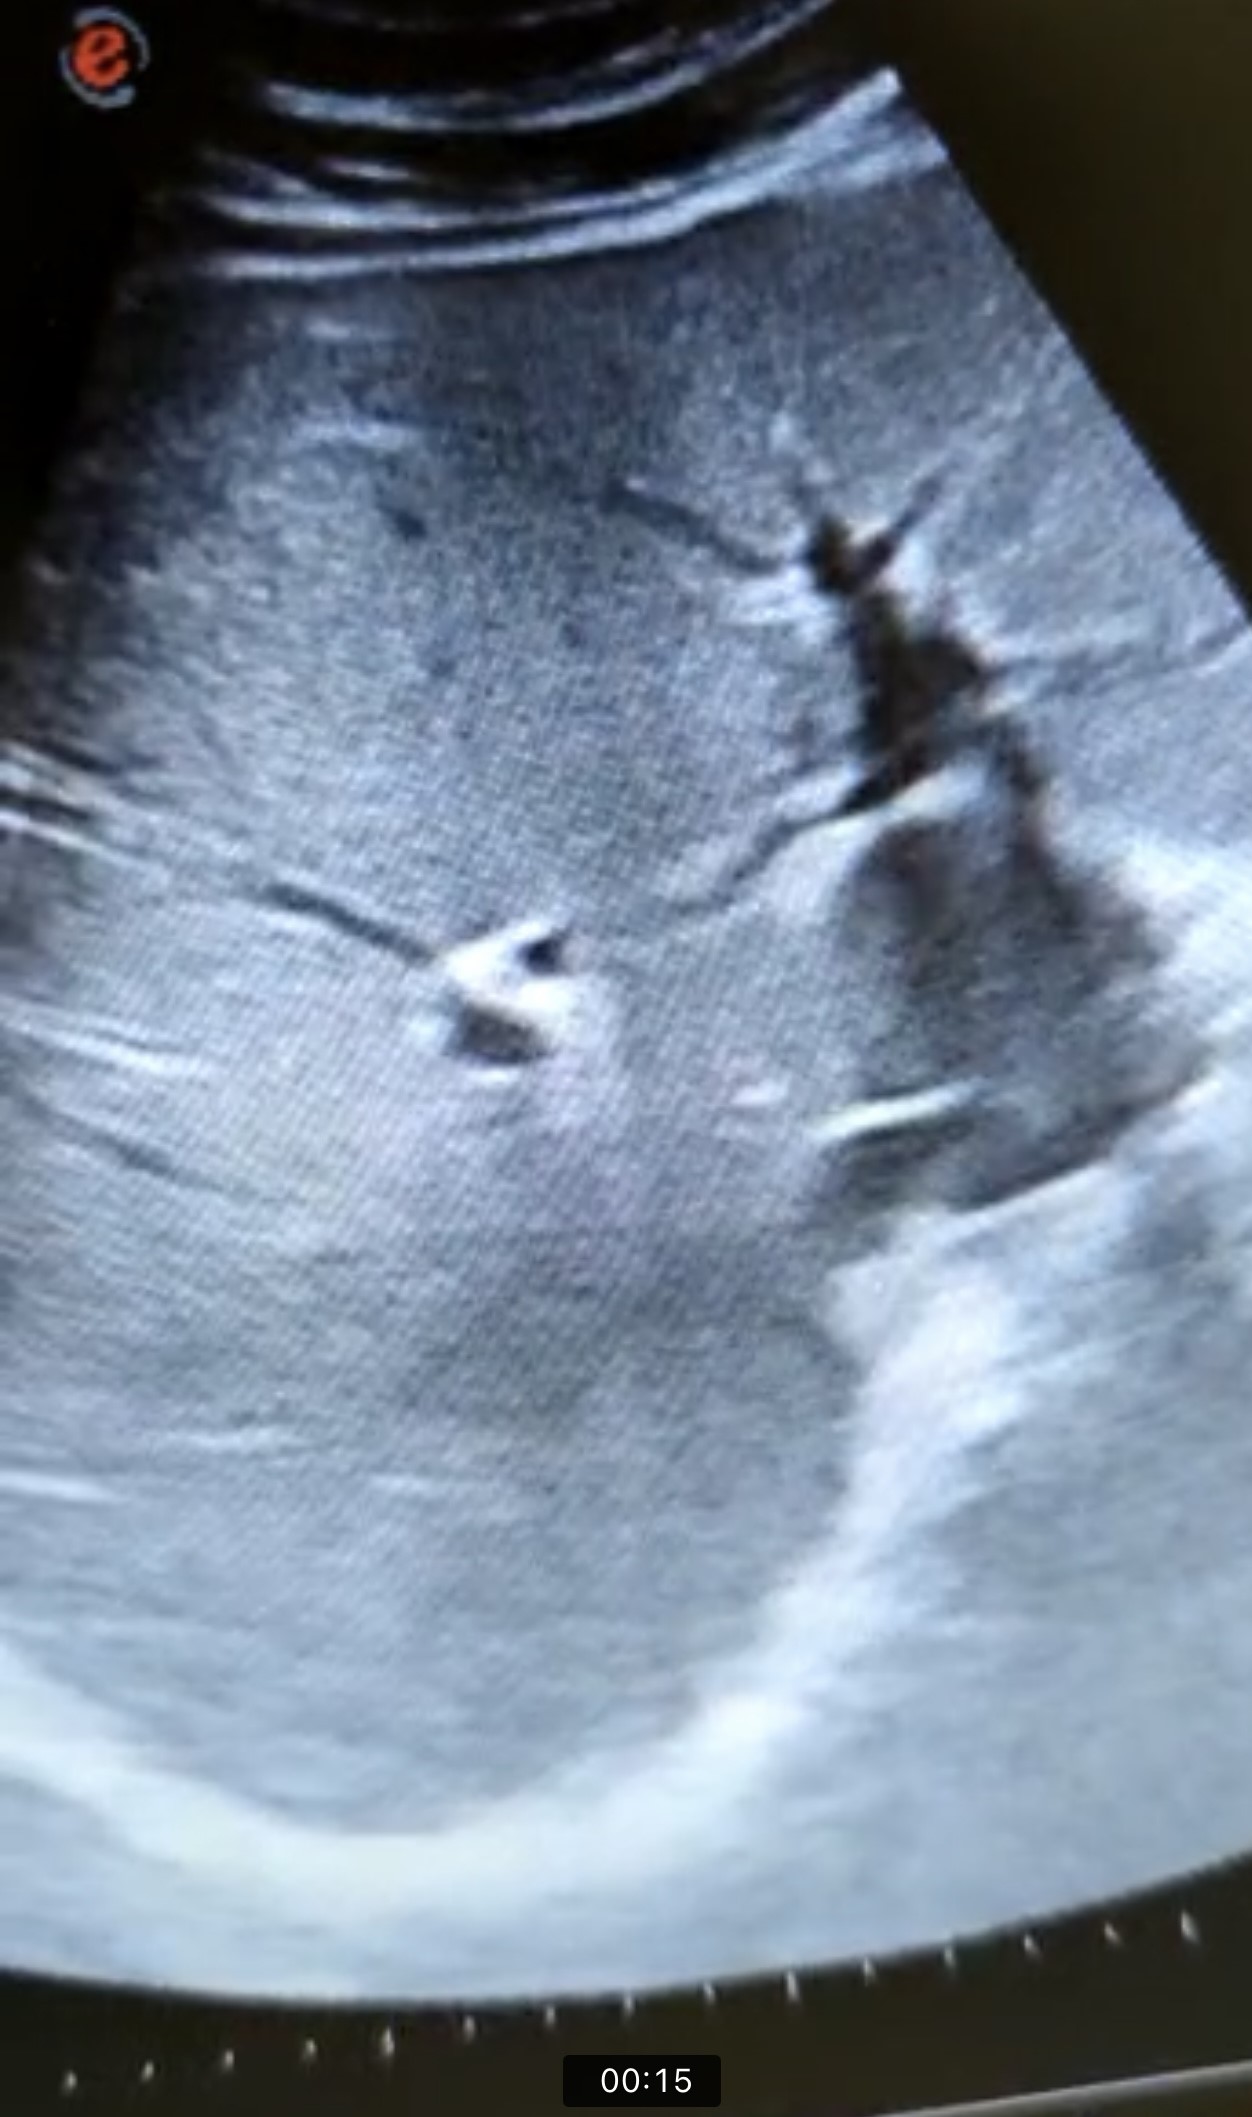

En la ecografía se observa ectasia de la vía biliar intrahepática conformando un patrón de doble carril.

Durante el ingreso se completa estudio con colangioRMN, que no es diagnóstica y TC ABDOMEN: que muestra un proceso neoformativo del colédoco medio compatible con colangiocarcinoma.